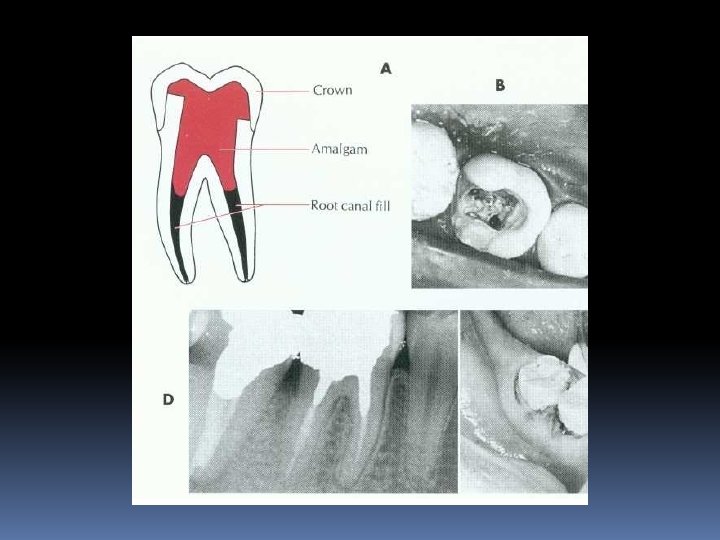

Post–core (Post Kor) nedir ? Post-kor, kronunun büyük kısmını kaybetmiş bir dişin kök kanalı içine yerleştirilmiş bir post’tan destek alarak kron kısmının oluşturulması demektir.

• Endodontik tedavi gören dişlerde, kök kanal girişinin açılması ya da çürük, kırık gibi nedenlerle aşırı madde kaybı bulunabilir. • Bu dişler kırılmaya karşı koruma altına alınmalıdır. • Bu amaçla, kök kısmında hazırlanan uygun bir kaviteye, yine uygun çap ve boyda bir post konularak tutuculuk; kron kısmına yapılan restorasyon yani kor ile de yapıya kron içi desteklik sağlanır.